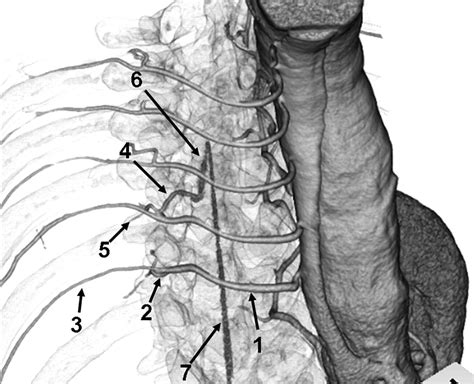

Typically, this artery arises from the aorta between the levels of T8 and L1. However, it is important to note that its origin can be highly variable, sometimes appearing as high as T5 or as low as L2. The vessel travels through the intervertebral foramen, usually on the left side (in about 70-80% of cases), before joining the anterior spinal artery to provide the bulk of the blood supply to the thoracolumbar spinal cord.

• Origin: Most commonly T8-L1 segmental arteries.

• Lateralization: Predominantly found on the left side of the body.

Identifying the Artery of Adamkiewicz prior to surgery is a diagnostic challenge due to its small caliber and variable anatomical path. Computed Tomography Angiography (CTA) has become the gold standard for non-invasive identification. Advanced software allows for multiplanar reconstruction, helping radiologists trace the “hairpin turn” appearance that is characteristic of this vessel as it enters the spinal canal.